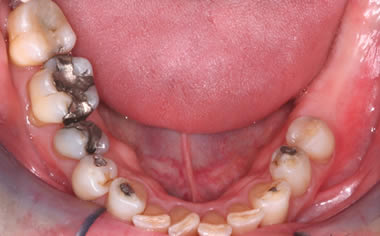

Missing lower teeth replaced by three dental implants and crowns.

Six missing lower back teeth replaced by dental implants